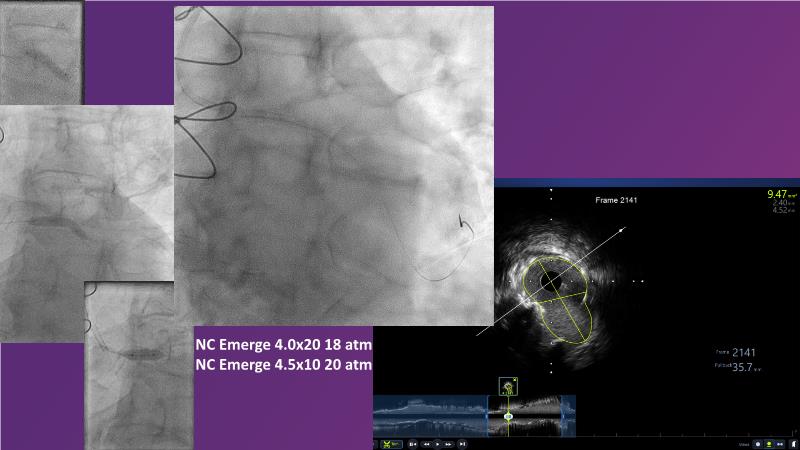

Don't miss this session for expert guidance on preparing and managing complex lesions. Gain insights into choosing the right tools, including microcatheters and balloons, for optimal treatment outcomes. Explore the innovative features of flagship devices for complex PCI, and Pronavi microcatheter and Alveo HP CTO balloon to treat complex CTO lesions. Learn about the safety and efficacy of the Wedge NC scoring balloon, the importance of using POT dedicated balloons in POT and DOT techniques, and get updated tips and tricks from ongoing clinical practices.

- To know the innovative features and capabilities of flagship devices in advancing complex PCI treatment

- To gain insights on Pronavi microcatheter and Alveo HP CTO balloon to treat complex CTO lesions, understand the safety and efficacy of lesion preparation with Wedge NC scoring balloon and the significance of using POT dedicated balloon in POT and DOT technique